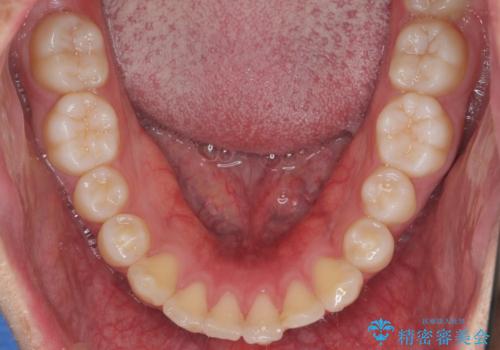

出っ歯の治療 インビザラインで抜歯矯正 親知らずを使用した矯正

- 出っ歯を主訴に来院。

上の小臼歯を2本抜歯しています。

そのかわり、上の親知らずを生かしており、歯の本数は減っていません。

矯正用ミニスクリューを使用しています(インプラント矯正)。

奥歯の歯ならびのずれが大きく、親知らずを抜いてすべて後ろに下げるか、手前の歯を抜いて前歯を下げるかの2択でした。

時間はかかりましたがしっかり前歯を下げて治療しています。